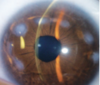

Anillo de Fleischer(SIGNO QUERATOCONO)

Anillo café encontrado en la base del cono formado por disposición de hierro en el epitelio basal, que se vuelve más estrecho y bien definido con la progresión de la enfermedad

Estrías de Vogt

líneas finas y paralelas observadas en el estroma posterior en el ápice del cono, que desaparecen con la aplicación de presión externa